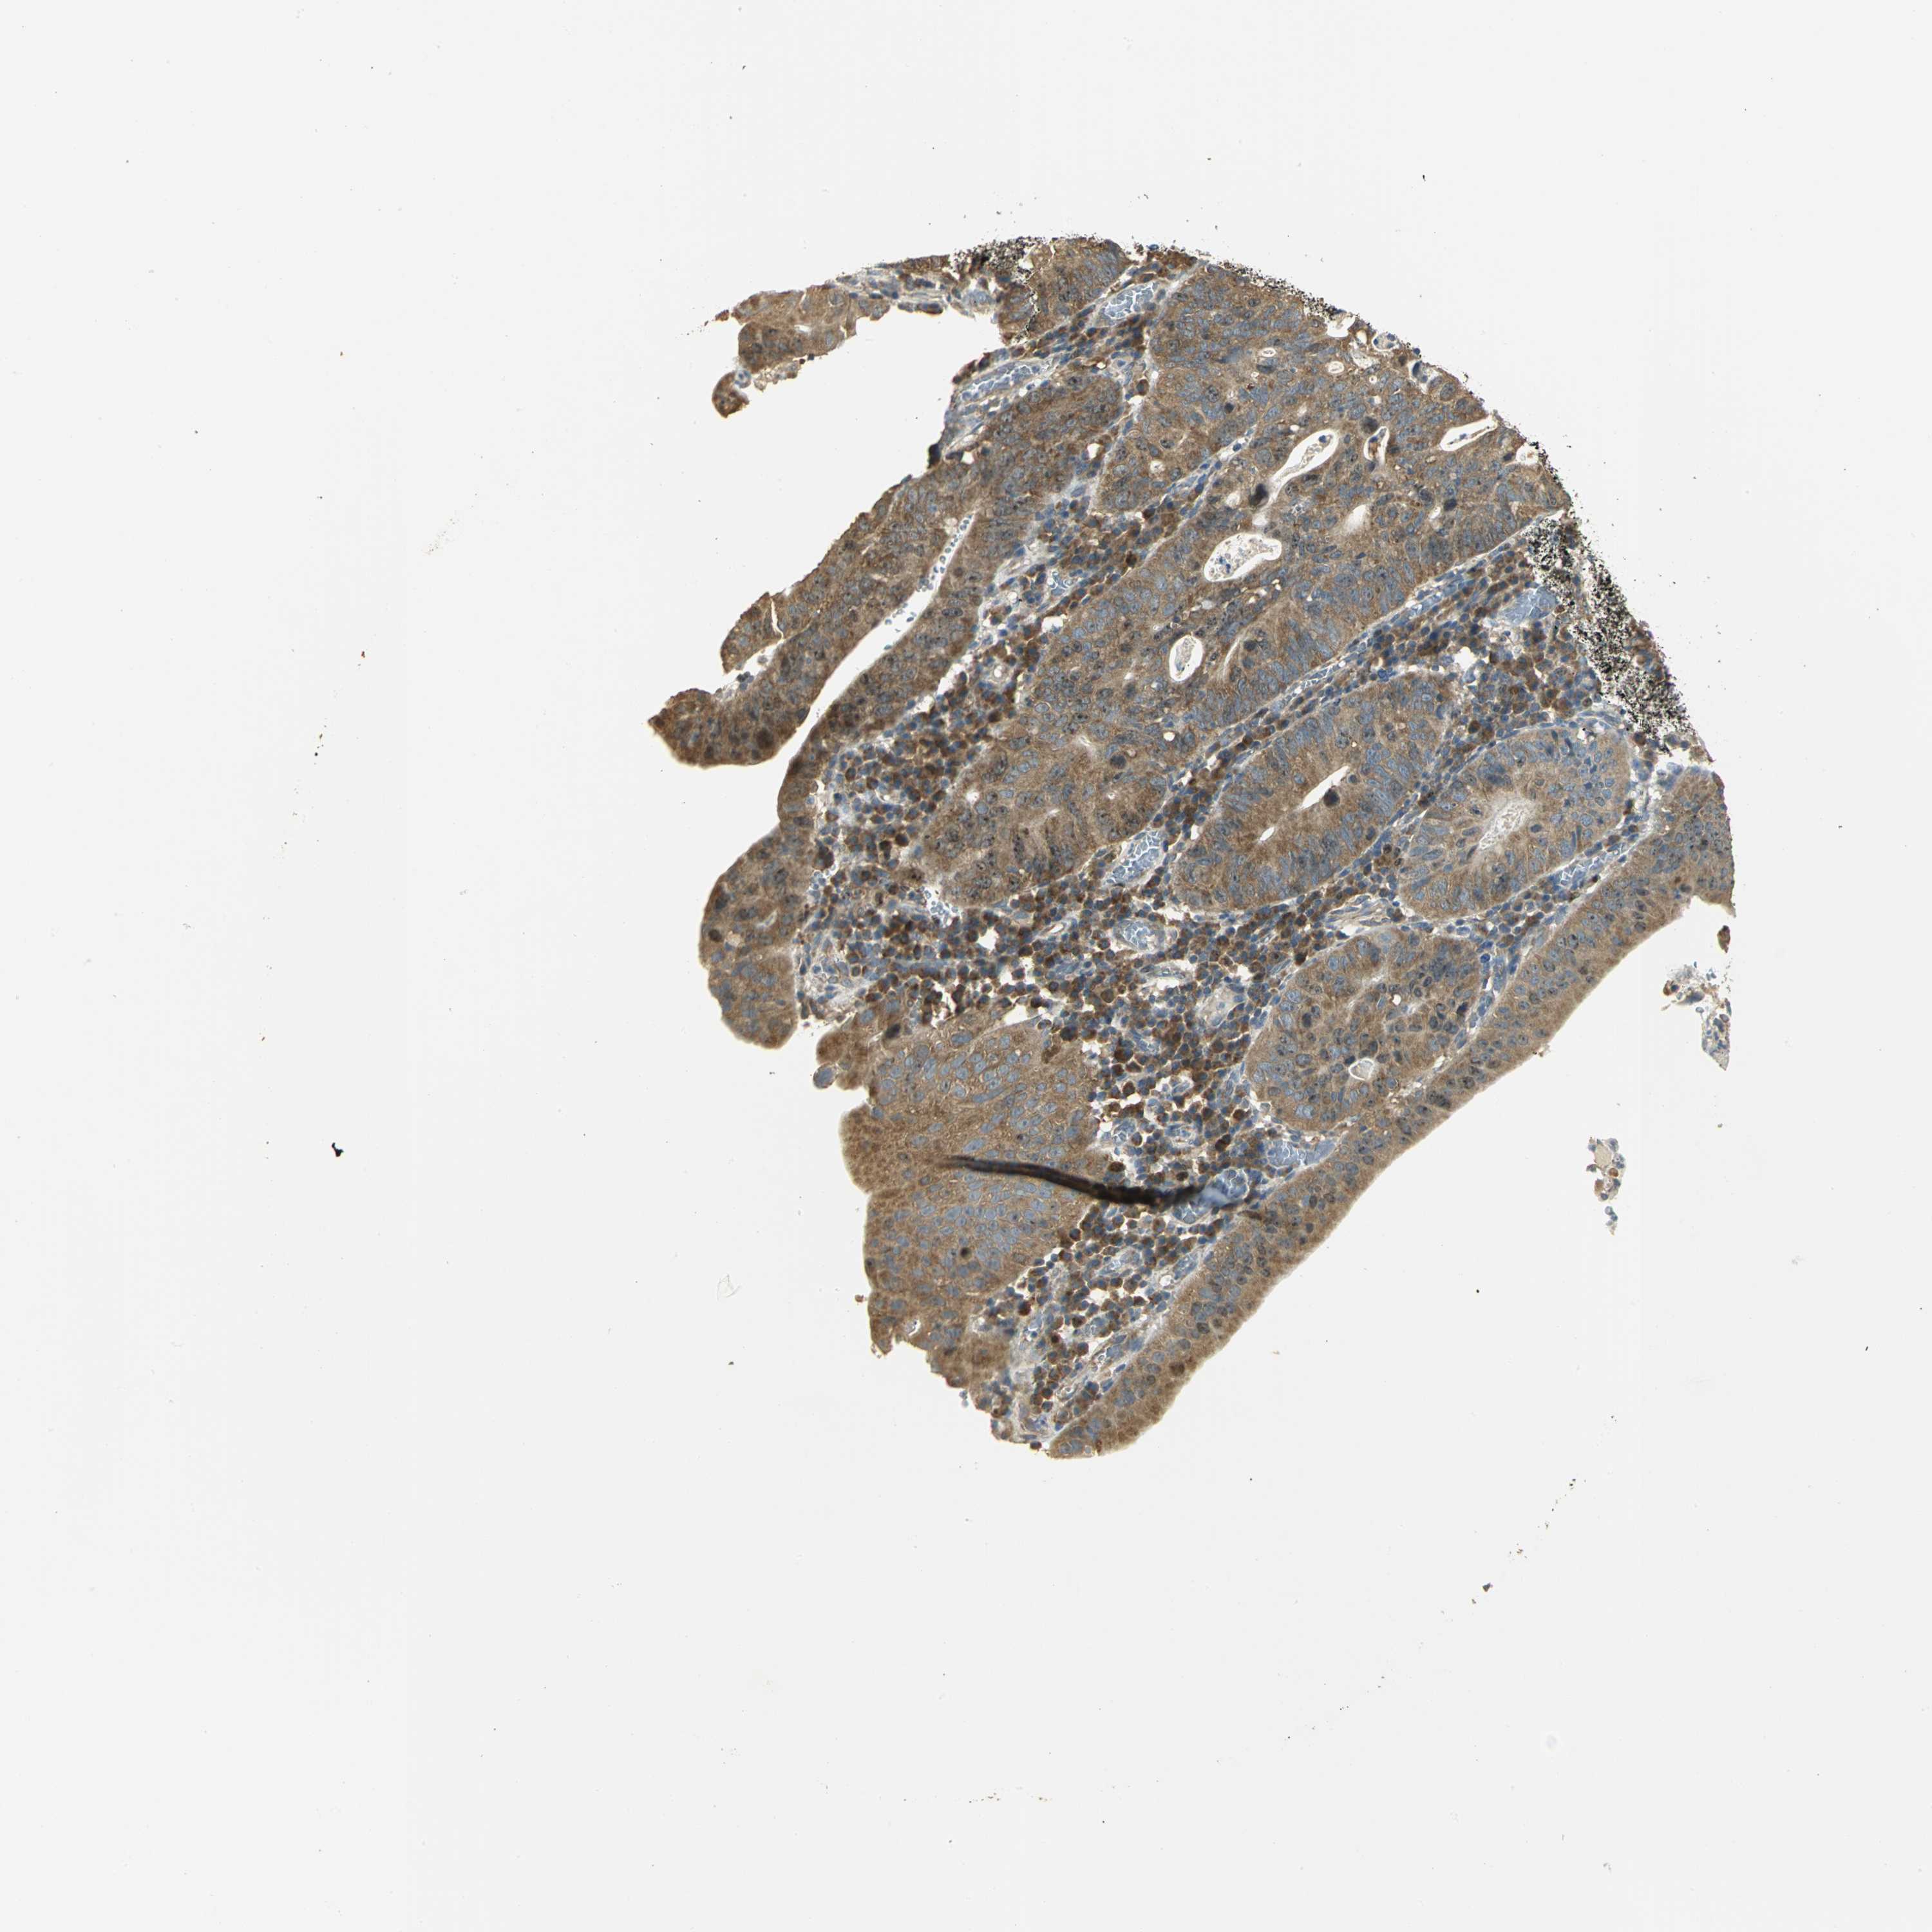

STOMACH CANCER - Protein expressioni

A mouse-over function shows sample information and annotation data. Click on an image to view it in a full screen mode. Samples can be filtered based on level of antibody staining by selecting one or several of the following categories: high, medium, low and not detected. The assay and annotation is described here.

Note that samples used for immunohistochemistry by the Human Protein Atlas do not correspond to samples in the TCGA dataset.

Antibody stainingi

Antibody staining in the annotated cell types in the current human tissue is reported as not detected, low, medium, or high, based on conventional immunohistochemistry profiling in selected tissues. This score is based on the combination of the staining intensity and fraction of stained cells.

Each image is clickable and will lead to virtual microscopy that enables deeper exploration of all samples and also displays staining intensity scores, fraction scores and subcellular localization as well as patient and tissue information for each sample.

Antibody HPA003979

Antibody HPA004130

Staining

High

Medium

Low

Not detected

Intensity

Strong

Moderate

Weak

Negative

Quantity

>75%

75%-25%

<25%

None

Location

Nuclear

Cytoplasmic/membranous

Cytoplasmic/membranous,nuclear

Adenocarcinoma, NOS

Adenocarcinoma, High grade